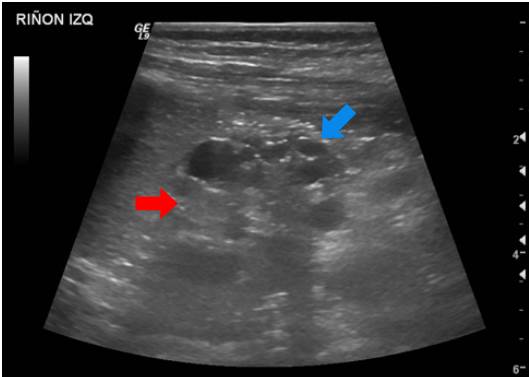

Se trató de un paciente de sexo masculino que a los dos años de vida presentó un cuadro clínico de lesión renal aguda KDIGO 3 en el contexto de una infección gastrointestinal 9. Se practicó una ecografía renal que evidenció la dilatación de las vías urinarias del lado derecho, por obstrucción secundaria a estenosis de la unión pieloureteral, con un riñón izquierdo de apariencia displásica multiquística (figura 1).

Análisis. Los riñones displásicos multiquísticos son masas renales no funcionales, causados por alteraciones en la diferenciación metanéfrica y caracterizados por la presencia de múltiples quistes que reemplazan en su totalidad el parénquima renal. Usualmente, se visualizan en la evaluación ecográfica prenatal; hay afectación de un solo riñón y tienden a involucionar en el útero o después del nacimiento en el 95 % de los casos. Esta condición suele ocurrir de manera esporádica; sin embargo, se han visto casos donde hay agregación familiar o puede presentarse en el contexto de condiciones multisistémicas por mutaciones en los genes EYA1, SIX1, HNF1B y PAX2, entre otros 10.